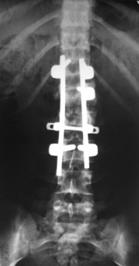

При малых сроках от момента травмы (от нескольких часов до 2-5 дней) операцию выполняли в объеме задней непрямой репозиции и стабилизации многоопорной металлоконструкцией с опорой на интактные тела позвонков в сочетании с задним локальным спондилодезом. При взрывном переломе тела одного позвонка осуществляли транспедикулярную фиксацию в пределах двух смежных позвоночно-двигательных сегментов с опорой на соседние интактные позвонки, непрямую репозицию тела сломанного позвонка. Завершали операцию формированием заднего локального спондилодеза вдоль металлоконструкции (рис. 10).

Рис. 10. Рентгенограммы пациента К. 16 лет. Взрывной перелом L1

А – КТ до операции; Б – после задней непрямой репозиции, транспедикулярной фиксации и заднего спондилодеза |